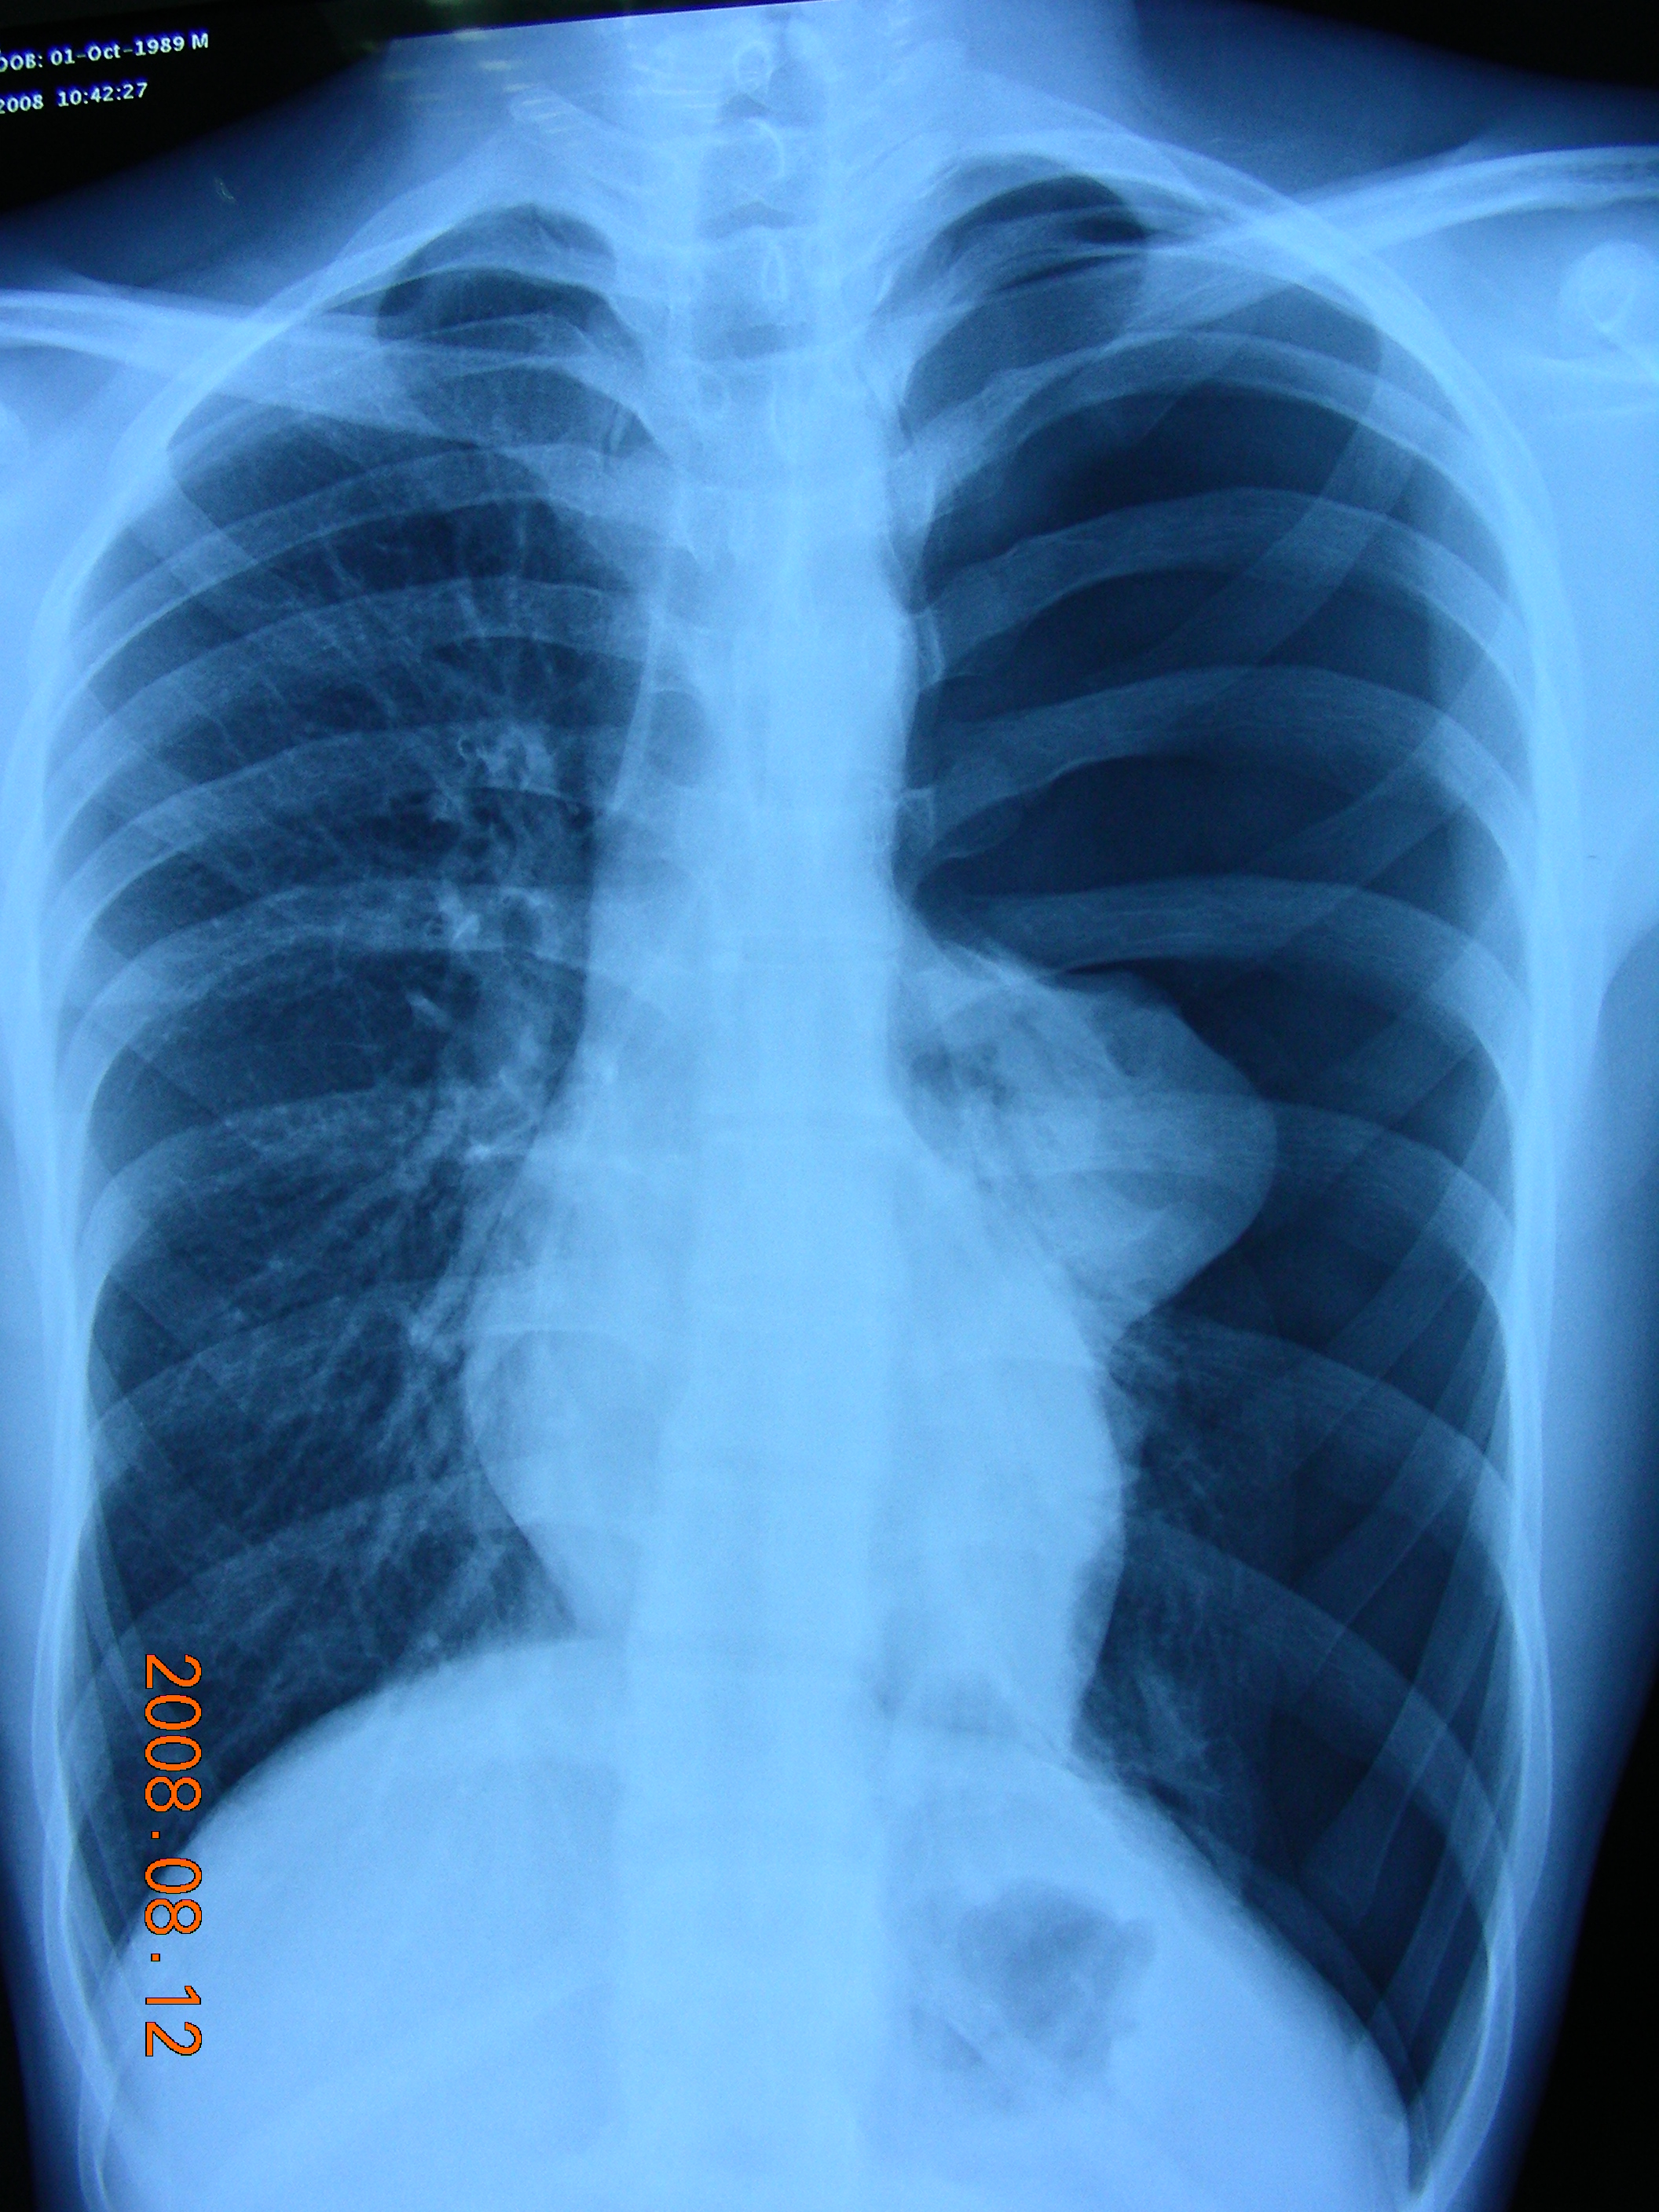

非创伤性脏层胸膜破裂而引起空气逸入胸膜腔称为自发性气胸。原发性气胸,又称恃发性气胸,指肺部常规X线检查未发现明显病变的“健康者”所发生的气胸。常见于20-40岁青壮年,瘦高体型男性较多。发生率大概8-10/100000,男多于女。 治疗:分为保守治疗(观察、胸腔闭式引流)和手术治疗。 保守治疗两年内平均可达25%以上,复发患者可达50%以。 手术目的:切除造成气胸的病灶并视情况性胸膜固定术,使气胸不致再发。 手术指征:①复发性气胸;②血气胸;③张力性气胸;④肺大泡明显者;⑤双侧气胸漏气严重、时间长,胸引效果不佳者;⑥居住地偏远;⑦工作性质特殊;⑧患者要求手术等等。 手术方式:胸部小切口或胸腔镜下行肺大泡切除、胸膜固定术。 (1)胸外科术前常规准备:血、尿常规,凝血II,肝肾功,免疫八项,血液生化检查;心电图,胸片检查等。 (2)向病人及家属交待病情和术中,术后可能发生的意外并行手术签字; (3)青霉素,普鲁卡因皮试试验,术前12小时禁食水。 3.手术当天可暂不进食,可经静脉输入糖、盐水、维生素等。 4.术后注意观察引流管是否通畅、引流液的颜色及引流量。 5.嘱患者深呼吸、咳嗽以促进气体的排出和肺的复张。